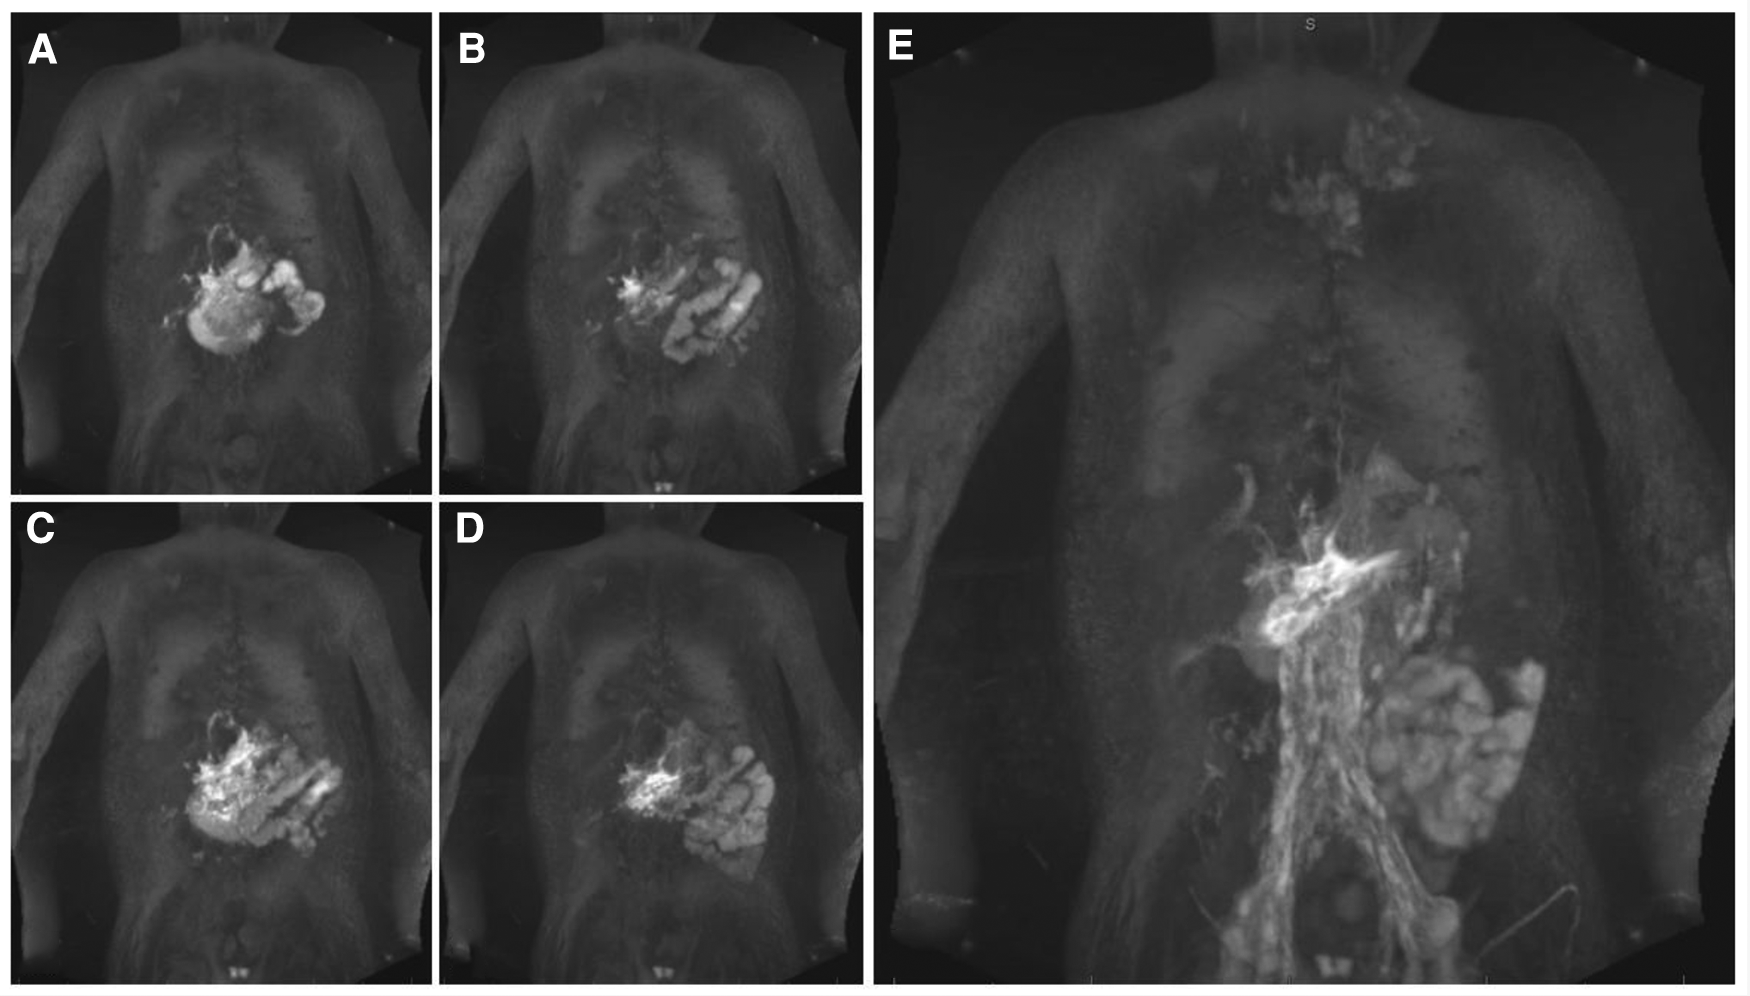

Figure 2

Pulmonary lymphatic perfusion syndrome. (A) Coronal projection of intranodal, intrahepatic and intramesenteric dynamic contrast magnetic resonance lymphangiography and (B) corresponding MIP T2 weighted lymphatic imaging demonstrating retrograde perfusion of the mediastinal, peribranchial- and pulmonary interstitial-lymphatic networks in a 3.2 year old patient with occluded thoracic outlet (type 4). (C) Coronal projection of intranodal dynamic contrast magnetic resonance lymphangiography and (D) corresponding MIP T2 weighted lymphatic imaging demonstrating a double thoracic duct in a 2.5 year old patient with the left duct supplying the lungs (type 3). (E) Typical airway cast in PB. MIP, maximal intensity projection; PB, plastic bronchitis.